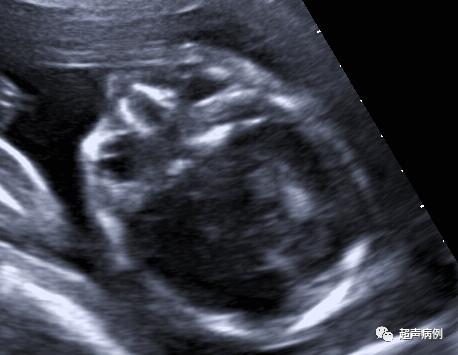

妇科医生也毫不知情,开的妇科超声检查,超声探头刚放上,“哦,怀孕了啊,停经多少周了?”

张珊差点从床上跳起来,瞪大眼睛问:“不可能吧?我还以为长肿瘤了。那大概多久怀上的?能流产吗?流产后还能再生孩子吗?”